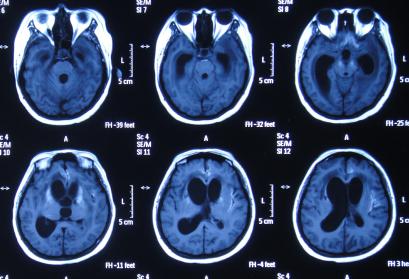

在第2家医院77天后即2015年11月20日,因患者意识呈昏睡状态,右侧肢体活动变更差,考虑结核可能更大,故转至第3家北京解放军某医院的结核科,入院时查PPD试验阳性,头部MRI示脑室扩张(图-18),给予异烟肼、利福平、乙胺丁醇,吡秦酰胺四联抗结核治疗,同时给予激素、营养支持治疗。

图-18:2015年11月20日头部MRI

第3家医院结核科治疗10天后即2015年11月30日,因脑室扩张加重,转至该院的神经外院,考虑双侧脑室不通,转入神外第2天即2015年12月2日接受了双侧脑室腹腔分流术及小脑病变活检术,术后当天查头部CT示双侧脑室分流术后状态(图-19)。

图-19:2015年12月2日头部CT